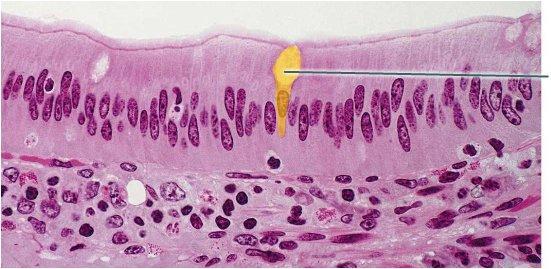

Which epithelial type is highlighted?

simple cuboidal epithelium

pseudostratified columnar epithelium

simple columnar epithelium

simple squamous epithelium

simple columnar epithelium

Which structures are highlighted?

cilia

microvilli

goblet cells

nuclei

microvilli

What is secreted by the highlighted cell?

bicarbonate rich juice

hormones

digestive enzyme

mucin

mucin

Which structures are highlighted?

nuclei

simple columnar cells

microvilli

goblet cells

goblet cells

Which structures are highlighted?

goblet cells

pseudostratified columnar epithelium

cilia

microvilli

cilia